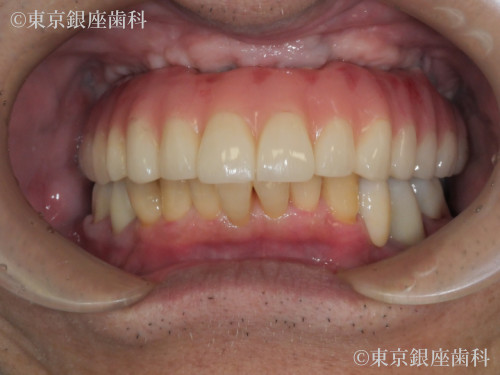

複数回の再埋入を経て骨と結合しづらい体質を克服した70歳代男性のインプラント症例

After

骨と結合しづらい体質でインプラントが抜けることが続いたが、材料変更(HAコーティング等)で改善。2年半かけ安定した状態に。

上顎ワンデイインプラント+骨造成+サイナスリフト